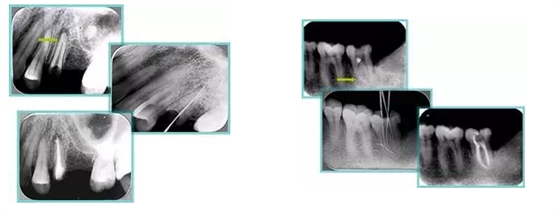

共有 4 張 X 線片,分別是術(shù)前、診斷絲 、主牙膠尖確認(rèn)、術(shù)后。

( 1 )術(shù)前:術(shù)前 X 線片用來了解牙齒的大概情況。術(shù)前預(yù)期為多根牙時(shí) X 線片應(yīng)偏頭拍攝。

( 2 )診斷絲:根據(jù)術(shù)前 X 線片進(jìn)行開髓、根管的初步預(yù)備后,需要插入診斷絲,用來指示工作器械位置。常用 10 號(hào)或 15 號(hào)擴(kuò)大器作為診斷絲插入牙髓腔。

( 3 )主牙膠尖確認(rèn):通過術(shù)前預(yù)期和診斷絲診斷,明確工作長度、牙根走向,進(jìn)行根管預(yù)備。之后應(yīng)進(jìn)行主牙膠尖(中銼)確認(rèn),已明確根管是否適合充填。

( 4 )術(shù)后:觀察治療效果。

6. 術(shù)后 X 線片

術(shù)后 X 線片用來評(píng)定根管充填 長度、致密度(管壁清晰、側(cè)枝)等指標(biāo)。

左圖為根管充填術(shù)后 X 線片。圖中可見,根管充填較好。右下圖有白色小點(diǎn),為側(cè)方加壓導(dǎo)致糊劑擠出所致,表明根管充填比較致密。